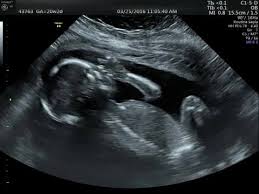

الجنين في الاسبوع العاشر من الحمل